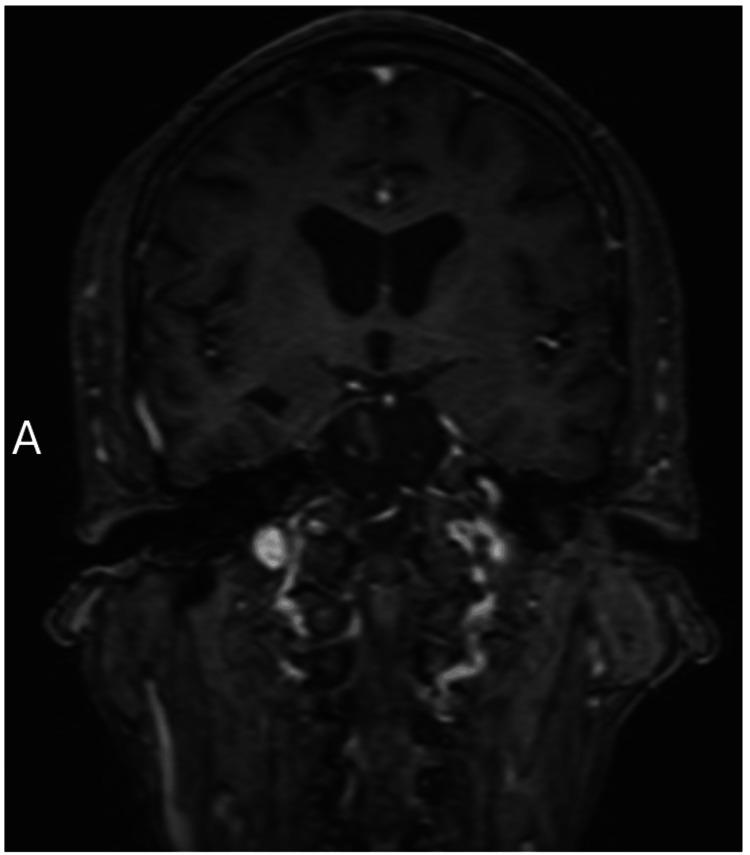

Anti-leucine-rich glioma-inactivated 1 limbic encephalitis (anti-LGI1 LE) is a rare autoimmune limbic encephalitis with a potentially misleading presentation that can delay diagnosis and treatment. The incremental progression of widely variable symptoms with a prominent behavioral disturbance can conceal the disease and prompt an initial psychiatric diagnosis. Although specific MRI findings ought to be evident by the time the disease progresses to frank limbic encephalitis, it appears inconsistent and ill-defined and is thus unreliable. Nevertheless, brain imaging remains prominent in the discussion, even included in some guidelines for diagnosing anti-LGI1 LE. Here, we present a case of a patient who presented after a suicide attempt with a long history of psychiatric issues, aberrant "spasms," and subsequently encephalopathy, who was eventually diagnosed with anti-LGI1 LE only after delayed CSF antibodies studies. In this patient, symptoms emerged over two years, with multiple brain MRIs being negative, including the one completed during the hospital admission in focus. The purpose of this case report is to encourage maintaining a broad differential when patients present with bizarre symptoms. This report underlies the importance of thorough clinical evaluation, utilization of multiple diagnostic resources, and the need for heightened awareness among healthcare providers about the subtleties of autoimmune encephalitis presentations. With anti-LGI1 LE already being severely underdiagnosed, it is important to continue reviewing various cases of patients who are diagnosed with anti-LGI1 LE and further review to understand its pathophysiology and common clinical presentation. This case also underscores the ongoing evolution in understanding anti-LGI1 LE and highlights that patients may present with unfamiliar symptoms or diagnostic challenges. The overall objective is to help providers recognize anti-LGI1 LE earlier, so treatment can be initiated sooner, leading to a better prognosis for patients.

抗富含亮氨酸胶质瘤失活1边缘性脑炎(抗LGI1边缘性脑炎)是一种罕见的自身免疫性边缘性脑炎,其临床表现可能具有误导性,会延迟诊断和治疗。症状广泛多样且渐进发展,伴有明显的行为障碍,可能掩盖病情并促使最初作出精神科诊断。尽管在疾病发展为明显的边缘性脑炎时,特定的磁共振成像(MRI)表现应该很明显,但它看起来并不一致且定义不明确,因此不可靠。然而,脑成像在讨论中仍然很突出,甚至被纳入了一些抗LGI1边缘性脑炎的诊断指南。在此,我们报告一例患者,该患者在有长期精神问题、异常“痉挛”病史后自杀未遂,随后出现脑病,最终仅在脑脊液抗体研究延迟后才被诊断为抗LGI1边缘性脑炎。在该患者中,症状出现超过两年,多次脑部MRI检查均为阴性,包括住院期间重点检查的那次。本病例报告的目的是鼓励在患者出现奇异症状时保持广泛的鉴别诊断。本报告强调了全面临床评估、利用多种诊断资源的重要性,以及医疗服务提供者提高对自身免疫性脑炎表现细微之处认识的必要性。鉴于抗LGI1边缘性脑炎的诊断严重不足,继续回顾已诊断为抗LGI1边缘性脑炎的各种病例并进一步研究以了解其病理生理学和常见临床表现非常重要。 本病例还强调了对抗LGI1边缘性脑炎认识的不断演变,并突出表明患者可能出现不常见的症状或诊断挑战。总体目标是帮助医疗服务提供者更早地识别抗LGI1边缘性脑炎,以便能更早开始治疗,从而为患者带来更好的预后。